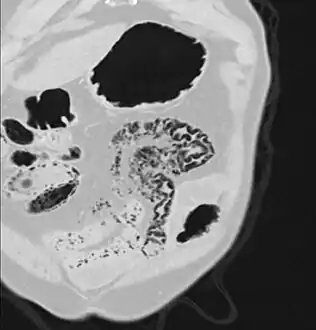

Pneumatosis intestinalis in the coronal computed tomography in lung window. It can be seen next to gas entrapment in the bowel wall and gas in the stomach wall and in numerous vessels, including the portal vein into the liver.

Pneumatosis intestinalis in computed tomography with intestinal ischemia. Lung window for better representation of the gas deposits in the intestinal walls.- Upright AP radiograph showing gas in the wall of the small bowel in the left upper quadrant indicative of pneumatosis intestinalis.

- Coronal reformatted MDCT image showing extensive pneumatosis intestinalis in the left upper quadrant small bowel. The pneumatosis is more cystic and nodular in the small bowel in the midline and the right of midline. This patient had a relatively benign presentation without bowel ischemia and was treated conservatively.